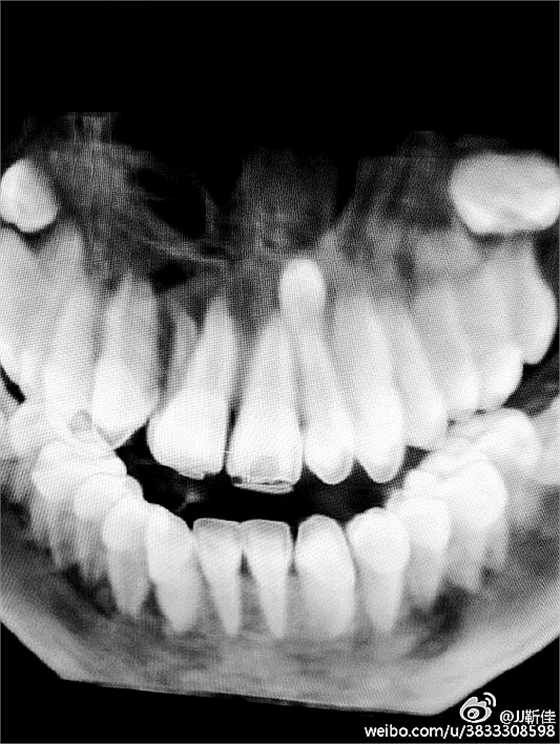

今年的額外牙真多啊 男孩14周。

ct定位